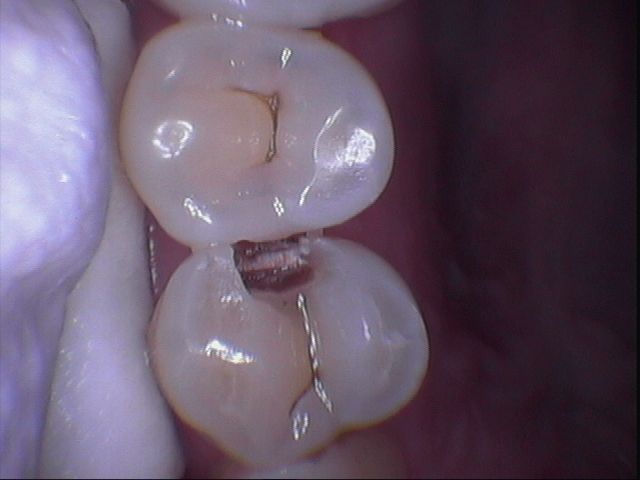

但是樹酯因為強度不足往往一段時間後,產生邊緣龜裂,與二次蛀牙這時候蛀牙範圍往往會比第一次更大,可以使用3D齒雕作修復, 提供牙齒良好的強度與美觀。

傳統金屬材料(銀粉)會熱脹冷縮,而且無法與琺瑯質連結在一起,太大的缺損在填補後經過一段時間容易與牙齒分開,導致二度蛀牙,導致齒質再破壞。

圖2較大的蛀洞可使用3D齒雕,保存較多牙齒結構,並提供足夠強度的支撐,恢復牙齒型態與功能。